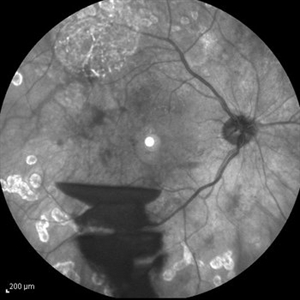

Endogenous Endophthalmitis Endogenous EndophthalmitisSep 3 2014 by Hamid Ahmadieh, MD Infrared image of the left eye of a 45-year-old diabetic man with the history of urinary tract infection. The most probable diagnosis was candida endogenous endophthalmitis. Photographer: Nayereh Hadipour, Negah Eye Center, Tehran, Iran Condition/keywords: candida endophthalmitis, endogenous endophthalmitis, infrared image

Endogenous Endophthalmitis Endogenous EndophthalmitisSep 3 2014 by Hamid Ahmadieh, MD Late phase FA image of the left eye of a 45-year-old diabetic man with the history of urinary tract infection. The most probable diagnosis was candida endogenous endophthalmitis. Photographer: Nayereh Hadipour, Negah Eye Center, Tehran, Iran Condition/keywords: candida endophthalmitis, endogenous endophthalmitis